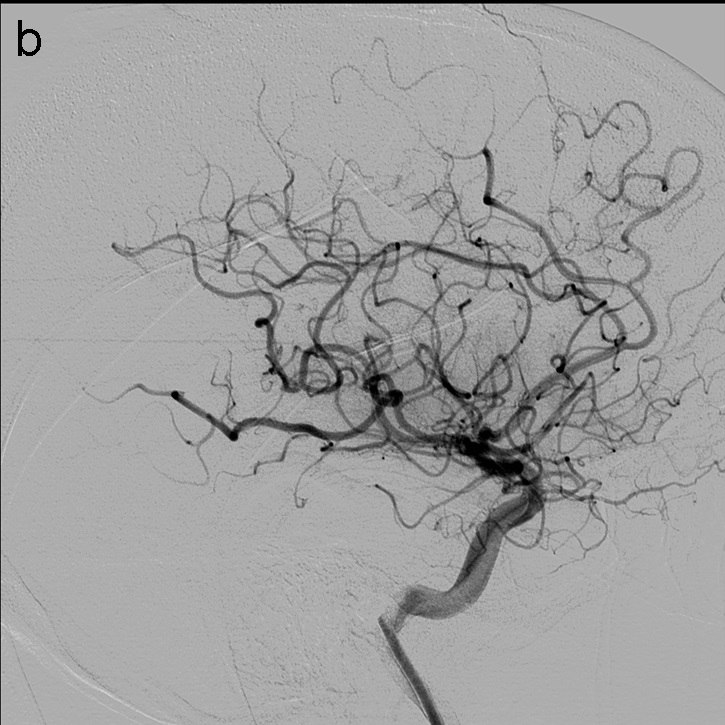

Se vuelve a realizar una serie a través del FlowGate2, en este caso demostrando una apertura completa de la ACM y sus ramas hemisféricas derechas, TICI 3 (imagen 5).